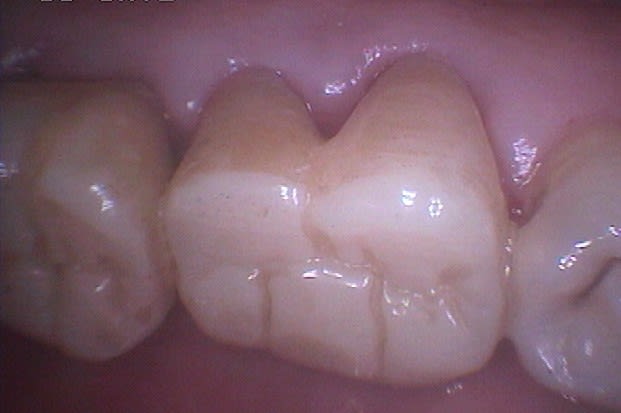

Marc, évidemment qu'il s'agit de gingivectomie, je dirais même plutôt gingivoplastie, la gencive est sculptée par le laser plus fidèlement qu'avec un bistouri ou une fraise car il suit exactement le trajet et la profondeur de chaque poche sans sectionner à l'emporte pièce.

J'ai rajouté les photos vestibulaires sur mon premier post, les poches étant un peu moins profondes qu'en palatin.